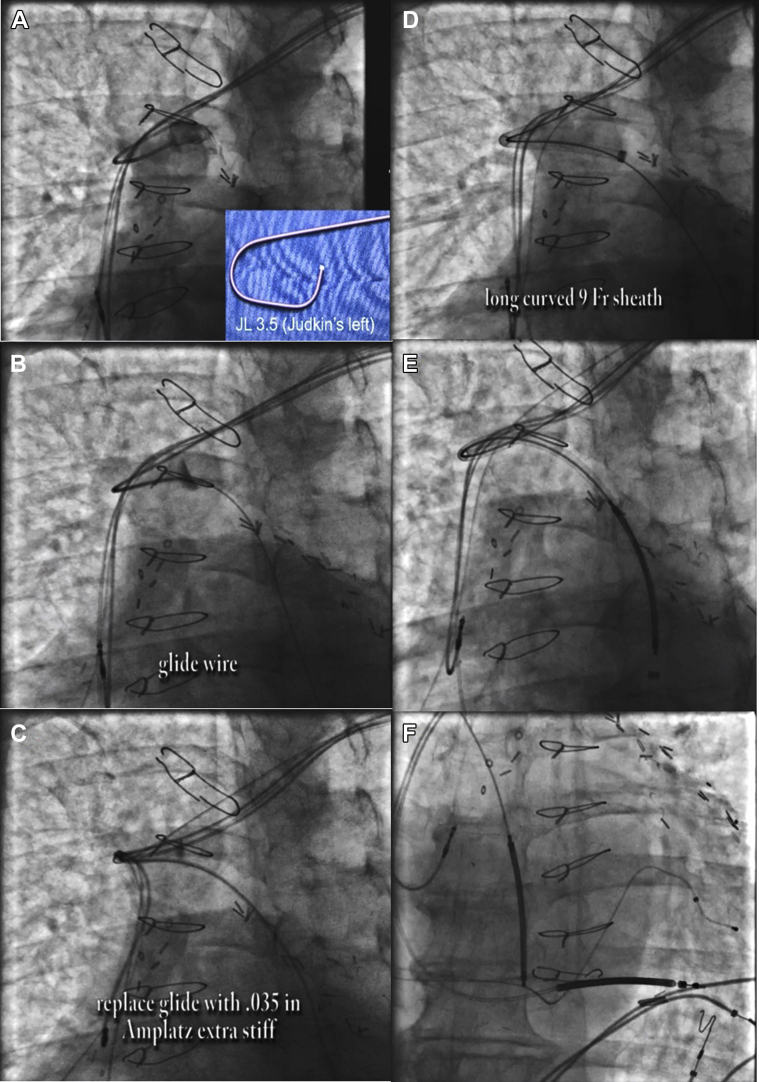

The axillary vein was cannulated distal to the previously implanted leads. A Judkins Left 3.5 diagnostic catheter was used to locate the azygos vein. Using a glide wire for support, the diagnostic catheter was advanced into the azygos vein and switched for an Amplatz wire. Over this, the Worley sheath was advanced far down the azygos vein. An ICD coil lead was then advanced into the azygos vein with subsequent defibrillation testing (Figure 2).

Figure 2.

Azygous coil implantation. A: A Judkins Left 3.2 diagnostic catheter was used to locate the azygos vein. B: Glide wire was used for support. C: The diagnostic catheter was switched for an Amplatz wire. D: Advancement of Worley sheath. E: Advancement of azygous coil. F: Final position of azygous coil.